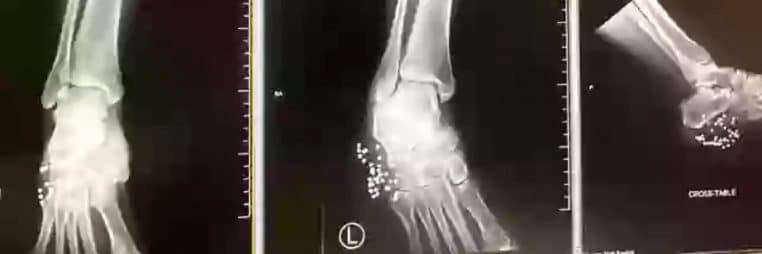

đ©Œ 40 plombs dans le pied, mais aucune amputation

Le choc est terrible : Marissa est transportĂ©e en urgence Ă l’University Hospital de San Antonio. LĂ -bas, les mĂ©decins dĂ©couvrent que pas moins de 40 fragments de plomb se sont logĂ©s dans son pied.

Les chirurgiens parviennent à retirer 20 fragments, mais il en reste encore autant enfouis dans les tissus. Marissa reste hospitalisée 10 jours, puis rentre chez elle, mais elle doit encore utiliser des béquilles et un fauteuil roulant. Une greffe de peau est prévue pour reconstituer la zone la plus endommagée.